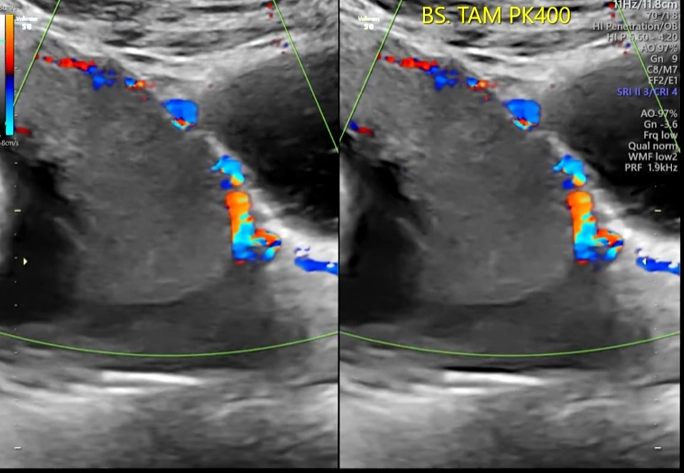

Nhau cuộn mép (Circumvallate Placenta)

16/03/2026